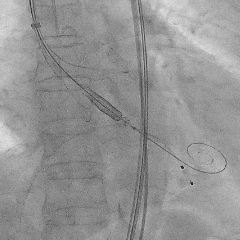

定位件入窦后造影

瓣膜释放